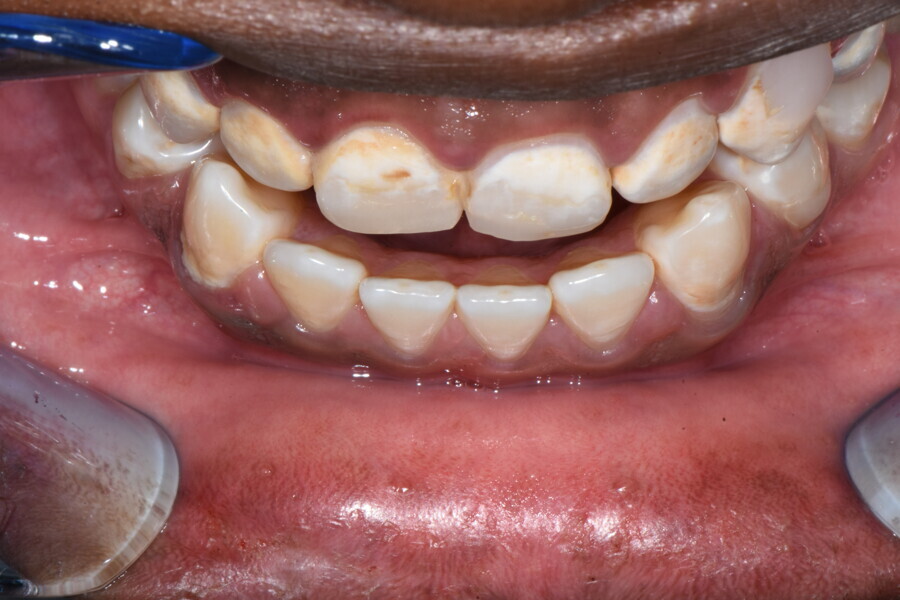

The 58-year-old patient wished to improve his oral aesthetics and function, complaining of mobility of the posterior teeth and wear of the anterior teeth. After data collection, a very complex situation was identified (Figs. 11–13):

1. severe periodontitis with poor prognosis of some teeth;

2. anterior crossbite;

3. severe wear mainly of the anterior teeth and compensatory eruption;38

4. atypical swallowing and lower posture of the tongue at rest;

5. masticatory dysfunction during the mastication test; and

6. no significant signs of temporomandibular disorder.

During the first visit, we checked the centric relation with cotton rolls, eliminating the posterior mesialising precontact and then performed a direct composite aesthetic and functional mock-up in this new position, not only to motivate the patient regarding the final result but also to help him understand better overall why tongue therapy, tooth alignment and dental resurfacing for augmentation of the vertical dimension of occlusion were required (Figs. 14 & 15).